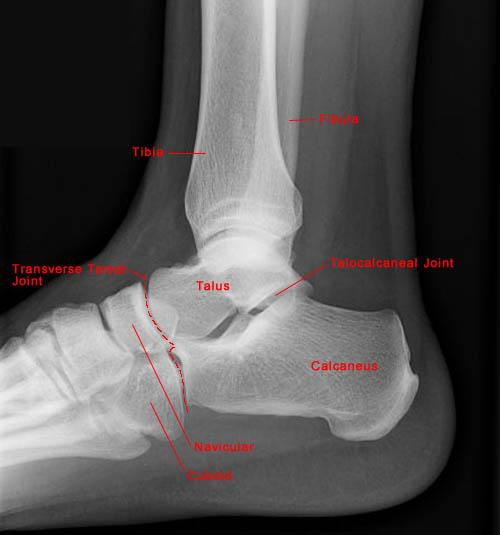

Запитання 56

СУГЛОБ УТВОРЕНИЙ СУГЛОБОВИМИ ПОВЕРХНЯМИ ЛАТЕРАЛЬНОЇ І МЕДІАЛЬНОЇ КІСТОЧКИ ТА ТІЛОМ ТАРАННОЇ КІСТКИ. РУХИ НАВКОЛО ФРОНТАЛЬНОЇ ОСІ. ЧАСТО - РОЗТЯЖІННЯ, ВИВИХИ, РОЗРИВИ, ПЕРЕЛОМИ. РОЗПІЗНАЙТЕ СУГЛОБ.

варіанти відповідей

КОЛІННИЙ С.

ГОМІЛКОВО-СТОПНИЙ С.

КУЛЬШОВИЙ С.

ЛІКТЬОВИЙ С.

ПЛЕЧОВИЙ С.

ПРОМЕНЕВО-ЗАП'ЯСТКОВИЙ С.